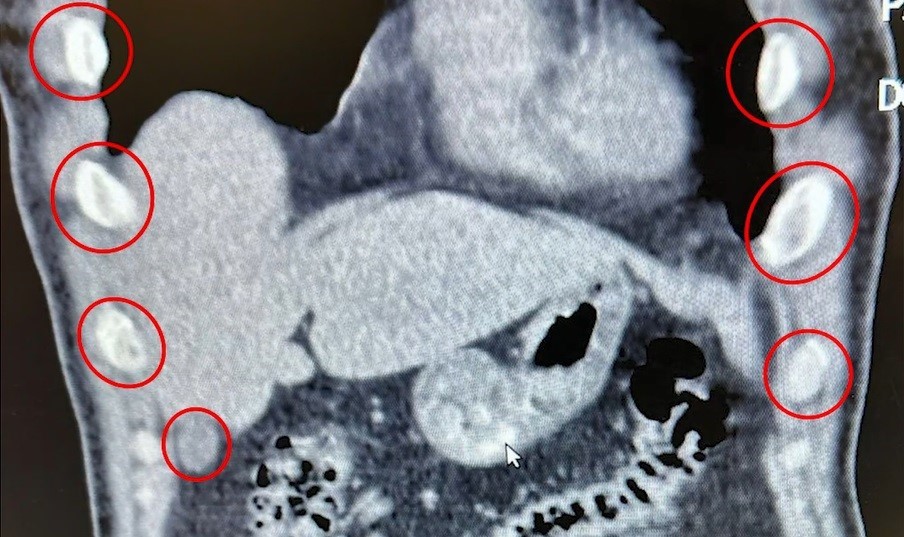

Uşak’ta midelerinden uyuşturucu çıktı: İranlı 3 kişi tutuklandı